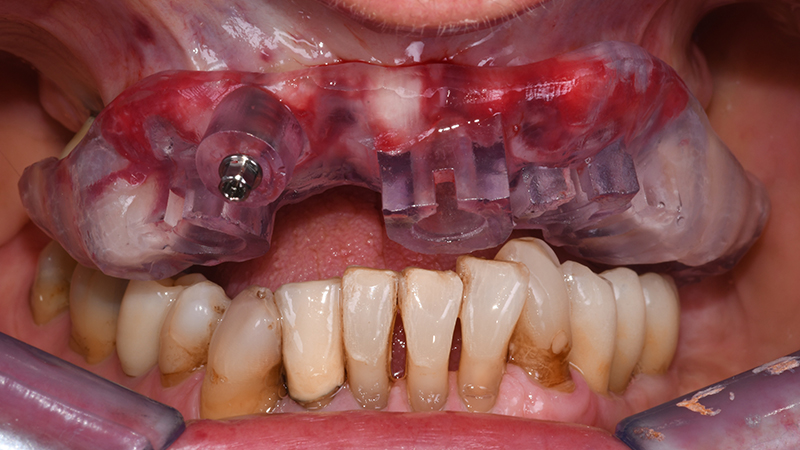

Dopo aver verificato la posizione della dima chirurgica sul modello digitale stampato, quest’ultima è stata posizionata in bocca tramite il supporto dentale dei settori latero-posteriori ed un pin di fissaggio è stato applicato (Anchor Pin Kit, Megagen, Daegu, Corea del Sud) (Figs. 7, 8, 9)

Visione frontale R2Guide in situ dopo applicazione pin di fissazione

Fig. 8 - Visione frontale R2Guide® in situ dopo applicazione pin di fissazione

Visione occlusale R2Guide

Fig. 9 - Visione occlusale R2Guide®